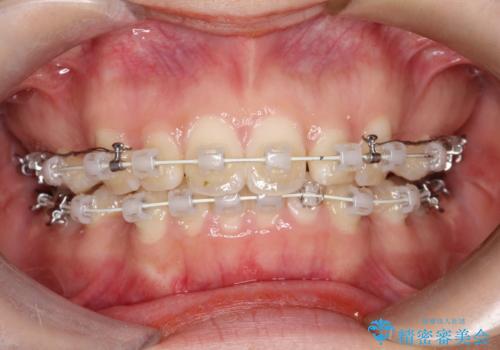

- 矯正装置

- 審美装置

- 横から見たときの口元が出てるの気になるとのことで来院されました。

口元の突出感と口唇の閉じずらさが確認されました。

上下左右の歯を1本ずつ、合計4本抜歯しして前歯を後方に下げて、口元の突出感を改善する計画としました。